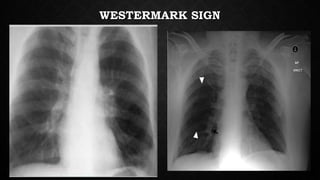

• Classically described signs such as the Hampton’s hump, Westermark

sign, Palla’s sign etc have a very poor sensitivity (<15%) and poor

positive predictive values.

WESTERMARK SIGN